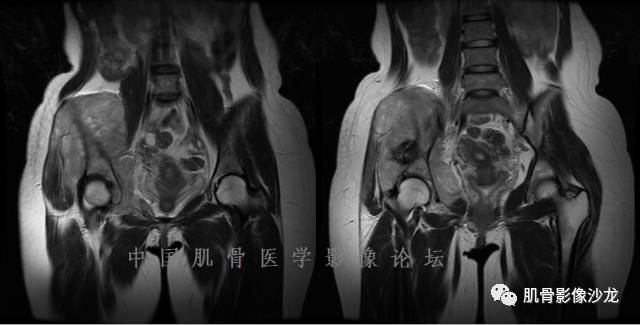

1、软骨肉瘤可以有膨胀性骨质破坏(病例3,4),可以有溶骨性骨质破坏(病例2),局部皮质因为破坏变薄,中断 ;

2、软骨基质T2WI高信号,软骨小叶分叶状,也就会出现高老师提到的骨内膜扇贝形压迹。一般认为骨内膜扇贝形压迹超过骨皮质厚度的2/3是软骨肉瘤在长管状骨的特征性表现。如上图。3、软组织肿块或肿胀;

4、 钙化,环形,弓形,边缘模糊 ;

5、增强后进行性延迟,不均匀分割状强化, 会强化的纤维间隔,软骨小叶不会强化,关于老师们说到的钙化,软骨肉瘤不一定会有钙化 。

2、软骨肉瘤的发病部位排名:最好发部位为髂骨,其次股骨、肱骨和脊柱。